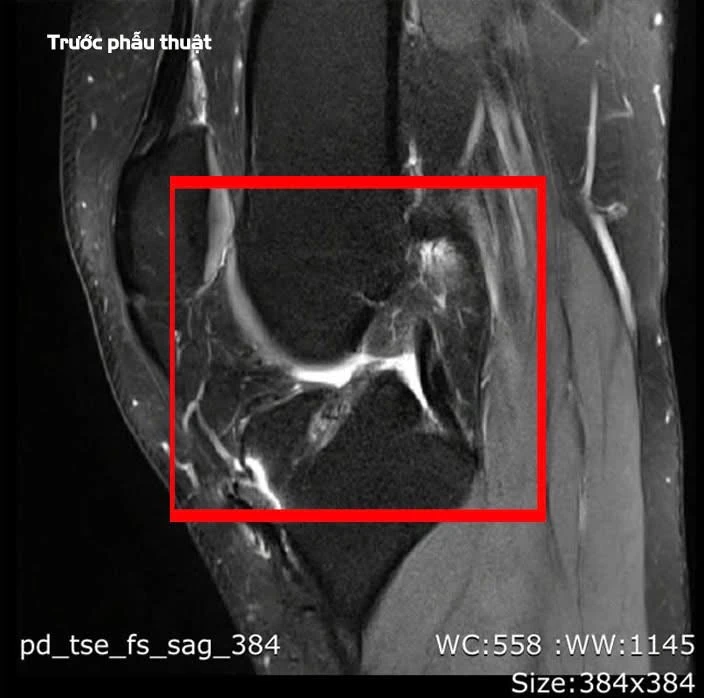

Bệnh nhân bị đứt hoàn toàn dây chằng chéo trước. Ảnh: BVCC

Theo bác sĩ chuyên khoa II, Lê Hoàng Văn Hải - Trưởng khoa Chấn thương Chỉnh hình qua thăm khám lâm sàng và chụp cộng hưởng từ (MRI), cho thấy bệnh nhân bị đứt hoàn toàn dây chằng chéo trước.